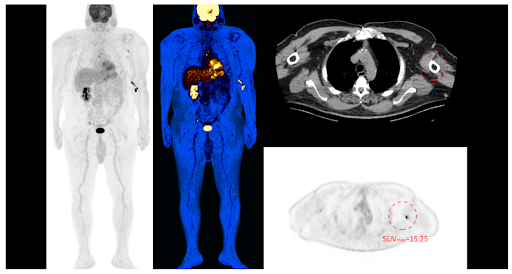

40.3 BMI Patient Imaging

2.2mm small Lesion detection